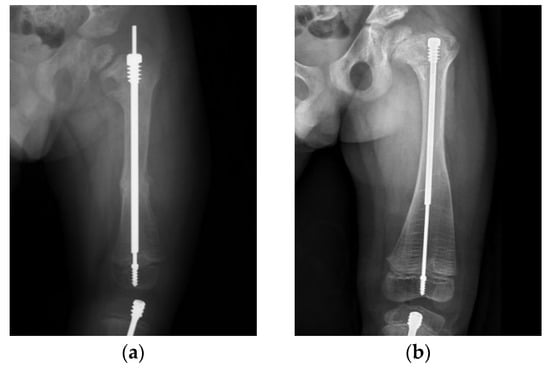

An 11-year-old boy with type IV OI (Figure 4) underwent revision surgery with an FD nail due to implant malposition. When the distal tip of a nail is not placed in the center of the joint, the mechanical axis may become deviated, possibly leading to refracture or nail bending (Figure 4a). In this patient, deviated alignment and a bowed femur caused an imbalance in mechanical stress, which led to a proximal femur refracture. Restoration of the alignment and bowing correction to avoid further implant failure were performed with a pediatric nail after physeal closure (Figure 4b).

Figure 4. Anteroposterior (AP) radiograph of the femur of an 11-year-old male post FD nail implantation. (a) The position of the male component was eccentric in the distal epiphysis. Due to an incorrect mechanical axis, subsequent refracture with nail bending was observed 3 years after surgery. (b) Revision surgery of osteoclasis and fixation with an interlocking PediNailTM.